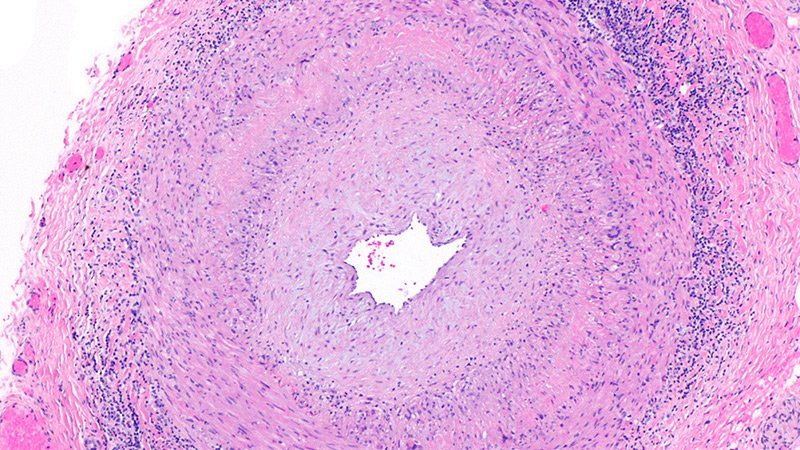

A key issue in GCA diagnosis is the need to confirm inflammation, Chévez-Barrios said. “The surgeon must obtain a significant portion of the artery, and the pathologist should review several sections and levels of the tissue to confidently say whether there is inflammation or no.”

In addition, the American College of Rheumatology recommends that patients with a high suspicion of GCA should begin corticosteroids as soon as laboratory studies are obtained; “As a result, if a TAB is performed after treatment begins, the typical active pattern of inflammation in the artery changes,” Chévez-Barrios said. “This further challenges the diagnosis in a frozen section setting because of the need for immunohistochemistry.” Although frozen sections are feasible in specialized settings such as the Mayo Clinic, most patients receive adequate diagnosis and treatment based on permanent sections.